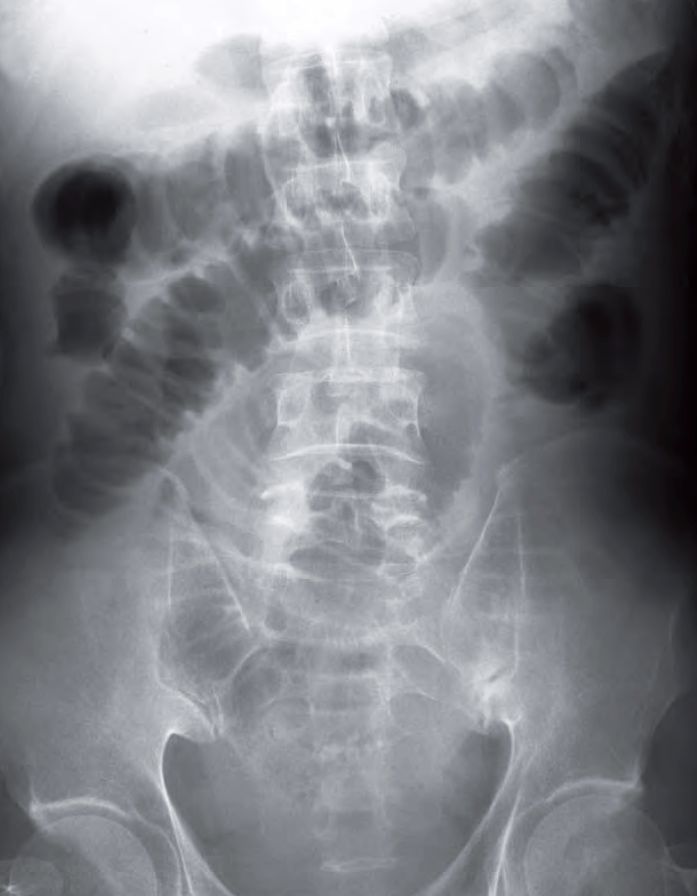

What radiological abnormalities can you identify on this radiograph ?

- There are multiple dilated bowel loops roughly central abdominal in location.

- Valvulae conniventes appearing as striations crossing completely across the width of the bowel loops.

Diagnosis: Small Bowel Obstruction